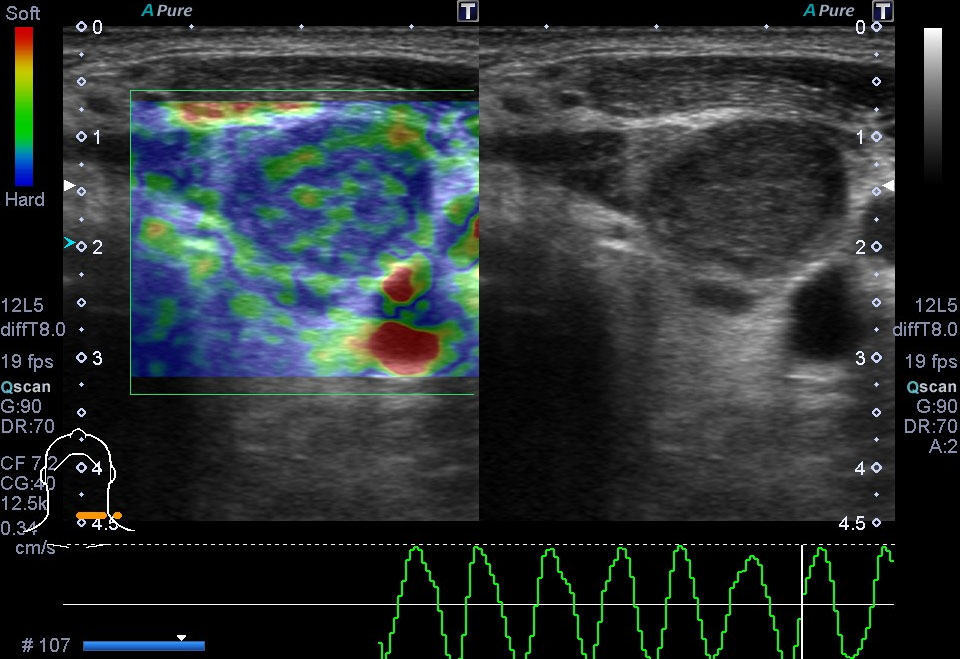

超音波(エコー) 診断画像

- 内頸動脈狭窄

- 膀胱がん

- 粉瘤

- 膝窩靭帯炎

- 乳腺症

- 乳がん

- 転移性肝がん

- 胆嚢ポリープ

- 胆石

- 大腸がん

- 前立腺肥大・前立腺がん

- 静脈瘤

- 腎細胞がん

- 子宮筋腫

- 心エコー(大動脈弁・僧帽弁閉鎖不全症)

- 鎖骨上転移

- 頸部リンパ節転移

- 胃がん

- バセドウ病